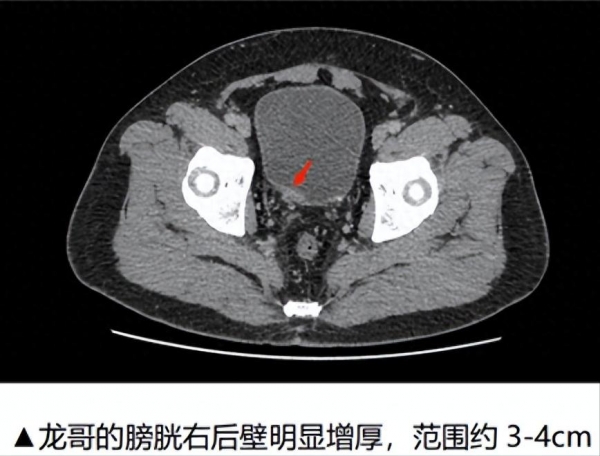

经过详细检查发现,龙哥的膀胱右后壁明显增厚,范围约3-4cm,而且位置离右侧输尿管开口很近,如果不尽快进行治疗,有可能进一步生长,严重的可能需要切除膀胱。